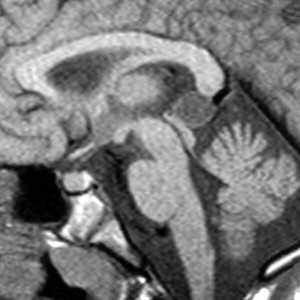

Липома представляет собой скопление в субарахноидальном пространстве зачаточных жировых клеток с примесью коллагена. Происходят липомы из остатков примитивной эмбриональной оболочки. Эта мальформация оболочек мозга связана с нарушением дифференцировки мезенхимы на мягкую мозговую оболочку и субарахноидальное пространство. Частота липомы составляет менее 0.5% от внутричерепных образований. Обычно липомы локализуется в мозолистом теле, в межполушарной щели, воронке гипофиза и гипоталамусе, реже вокруг червя мозжечка и пластины четверохолмия и мосто-мозжечковом углу и Липомы мозолистого тела сочетаются с его агенезией и в 60% случаев с распространением на сосудистое сплетение. При МРТ головного мозга липома четко очерчена, без отека вокруг и масс-эффекта, кость не разрушает. Структура образования чаще однородная, жировой интенсивности сигнала - то есть выраженно гиперинтенсивная на Т1-взвешенных МРТ и немного менее интенсивная по отношению к ликвору на Т2-взвешенных МРТ. Иногда встречаются неоднородные липомы с участками низкого сигнала от кальцинатов и сосудов, проходящих ее насквозь. При сомнениях в диагнозе надо выполнить МРТ головного мозга с подавлением жира или можно сделать КТ. На КТ липома всегда резко гиподенсна и может содержать включения кальция.

МРТ головного мозга. Сагиттальная Т1-взвешенная МРТ. Липома мозолистого тела.